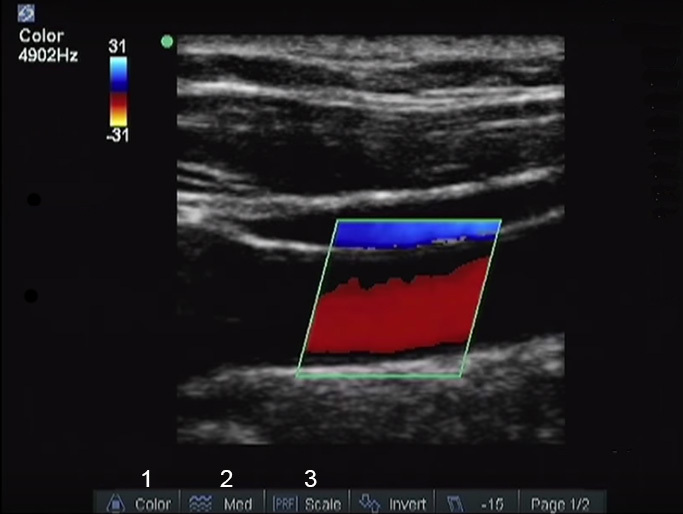

Ajustar la velocidad secuencial del Doppler en color

1. Color Gain (Ganancia de color)

2. Optimización del flujo (Alto - Medio - Bajo)

3. Escala de la FRI